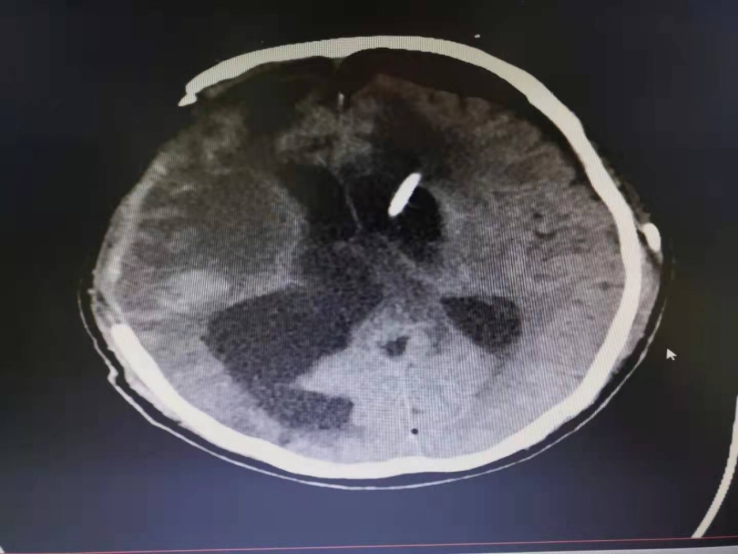

患者李某,男性,68岁,因外伤于外院转入我院治疗。患者为昏迷状态,完善头CT提示脑积水。从术前影像判断患者发病时间较长,长期处于昏迷状态,神经外二科经讨论后,决定行神经外科机器人辅助下脑积水分流手术,缓解颅内高压,改善患者预后。

术前影像

手术由高风全副主任医师和王庆历副主任医师共同完成,在神经外科机器人引导下,定位数据从术前CT上获得,以此作为定位依据确定穿刺点和靶点完成手术设计,精准打靶,成功完成立体定向下脑积水精准穿刺分流手术,术后脑积水完全缓解。